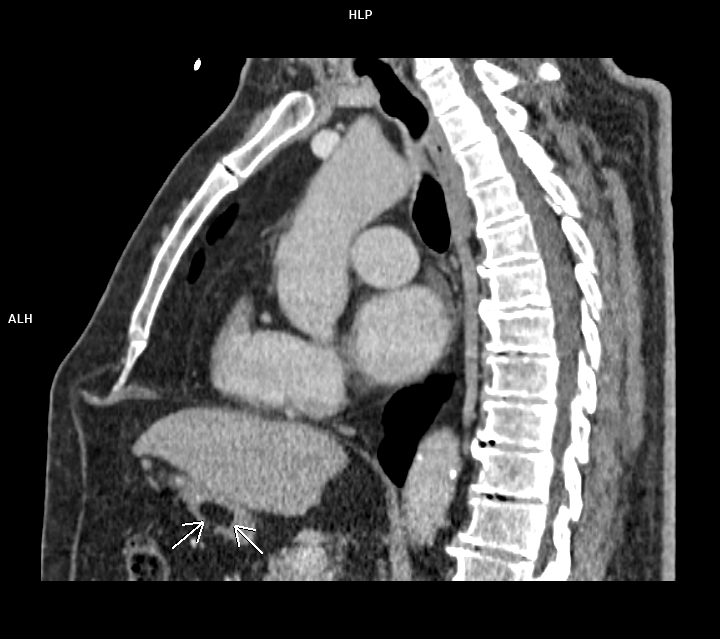

Figura 2: sagital CT postcontrast timp venos

Discuţie caz nr 89: lipomul de perete gastric este o tumoră benignă rară de origine mezenchimală ce este, de obicei, descoperire întâmplătoare sub formă unei arii circumscrise cu densități grăsoase ce sunt asimptomatice cand au dimensiuni mici. Sunt de obicei formate din celule grăsoase mature înconjurate de capsulă. Ca și în cazul nostru, sunt întâlnite mai frecvent în antrul gastric. Sunt diagnosticate prin CT deoarece au densități cuprinse între -70 și -120UH .

DE LUAT ACASĂ!!! Lipoamele gastrice sunt cel mai bine diagnosticate prin CT. Septurile fine ale țesuturilor moi probabil indică ulcerații sau modificări post-biopsie; liposarcomul gastric este extrem de rar. IRM-ul poate fi utilizat la copii sau la pacienții radiosensibili; tehnicile CT cu doze mici sunt de asemenea suficiente pentru diagnostic. Lipoamele mai mici de 3 cm sunt asimptomatice. Lipoamele simptomatice mai mari pot fi rezecate endoscopic dacă baza lor este mai mică de 2 cm; rezecția leziunilor cu baze mai largi a fost în mod tradițional retrogradată la rezecția chirurgicală, deși tehnici endoscopice mai noi s-au dovedit eficiente.